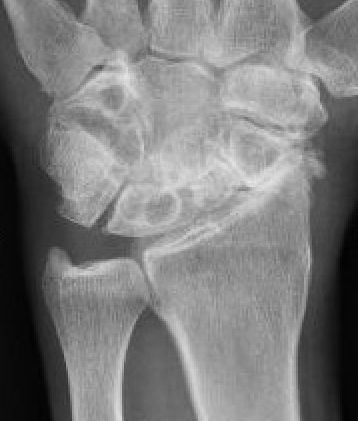

Scaphoid non union advanced collapse

Nonunion with resultant radiocarpal and midcarpal OA

Pathology

Scaphoid nonunion

- flexion deformity and abnormal joint mechanics

- radiocarpal osteoarthritis

- progresses from radial styloid / scaphoid fossa / midcarpal joint

- radiolunate joint preserved

Vender Classification

| Stage I | Stage II | Stage III |

|---|---|---|

|

Radial styloid and distal scaphoid fragment

+ Proximal scaphoid and capitate | + capitate-lunate joint |

MRI

- comparison of xray and MRI for grading SNAC wrist

- MRI better at detecting carpal OA